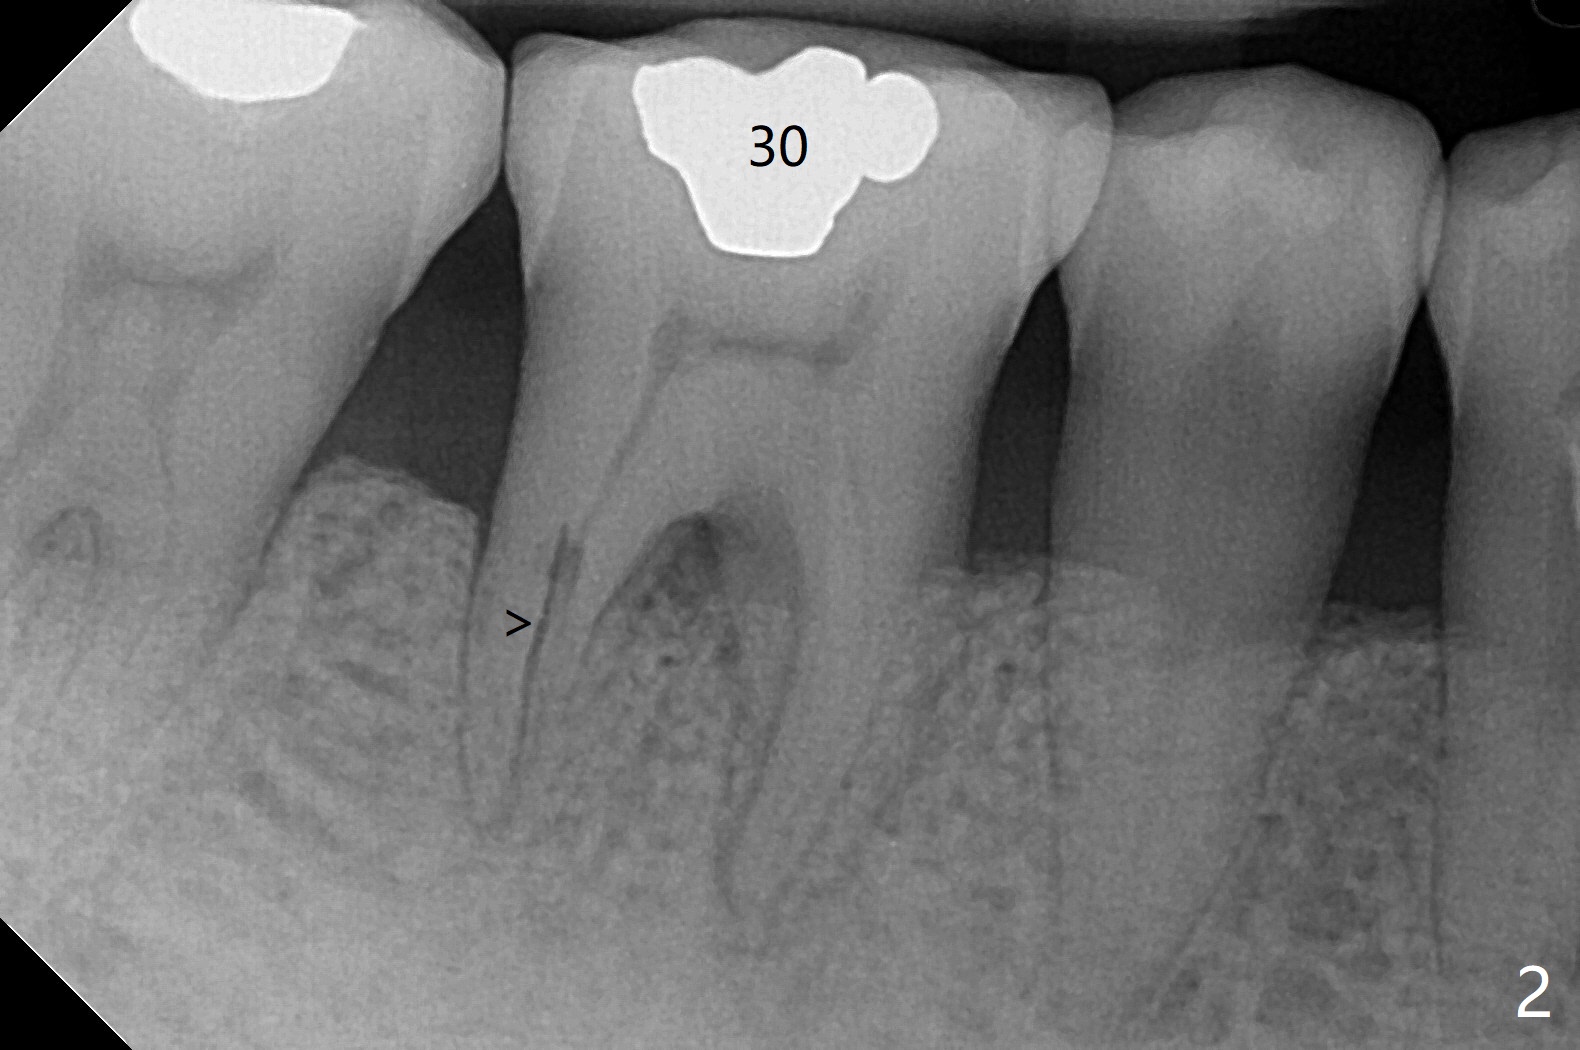

57岁女全口牙龈萎缩骨质吸收,其实卫生好,3号牙金属圈多年,治疗牙齿隐裂,骨质吸收和牙裂与咀嚼力大有关。最近抱怨19,30号牙敏感(图一),涂脱敏剂无效,拍摄根尖片(图二,三),显示30号牙远中根,19号牙近中根从牙槽嵴开始仿佛纵裂(图二,三),牙周探针患根周围触痛。磨牙牙根好像一段式植体,断裂总是发生于牙槽嵴顶,不过是横裂,所以一定要植入牙槽嵴之下,还要考虑今后牙槽嵴吸收。如何确诊牙根纵裂呢?例如19号牙CT显示颊侧近中根(图四,六:B)牙槽嵴处断裂(箭头)。利用一个叫Profile Program(Profilogram)测定近中根横断面平均密度,舌侧密度基本均匀(图七),而颊侧断裂处密度突然降低(图八)。当断裂还不是很明显时(隐裂),测定平均密度就显得重要,帮助诊断。